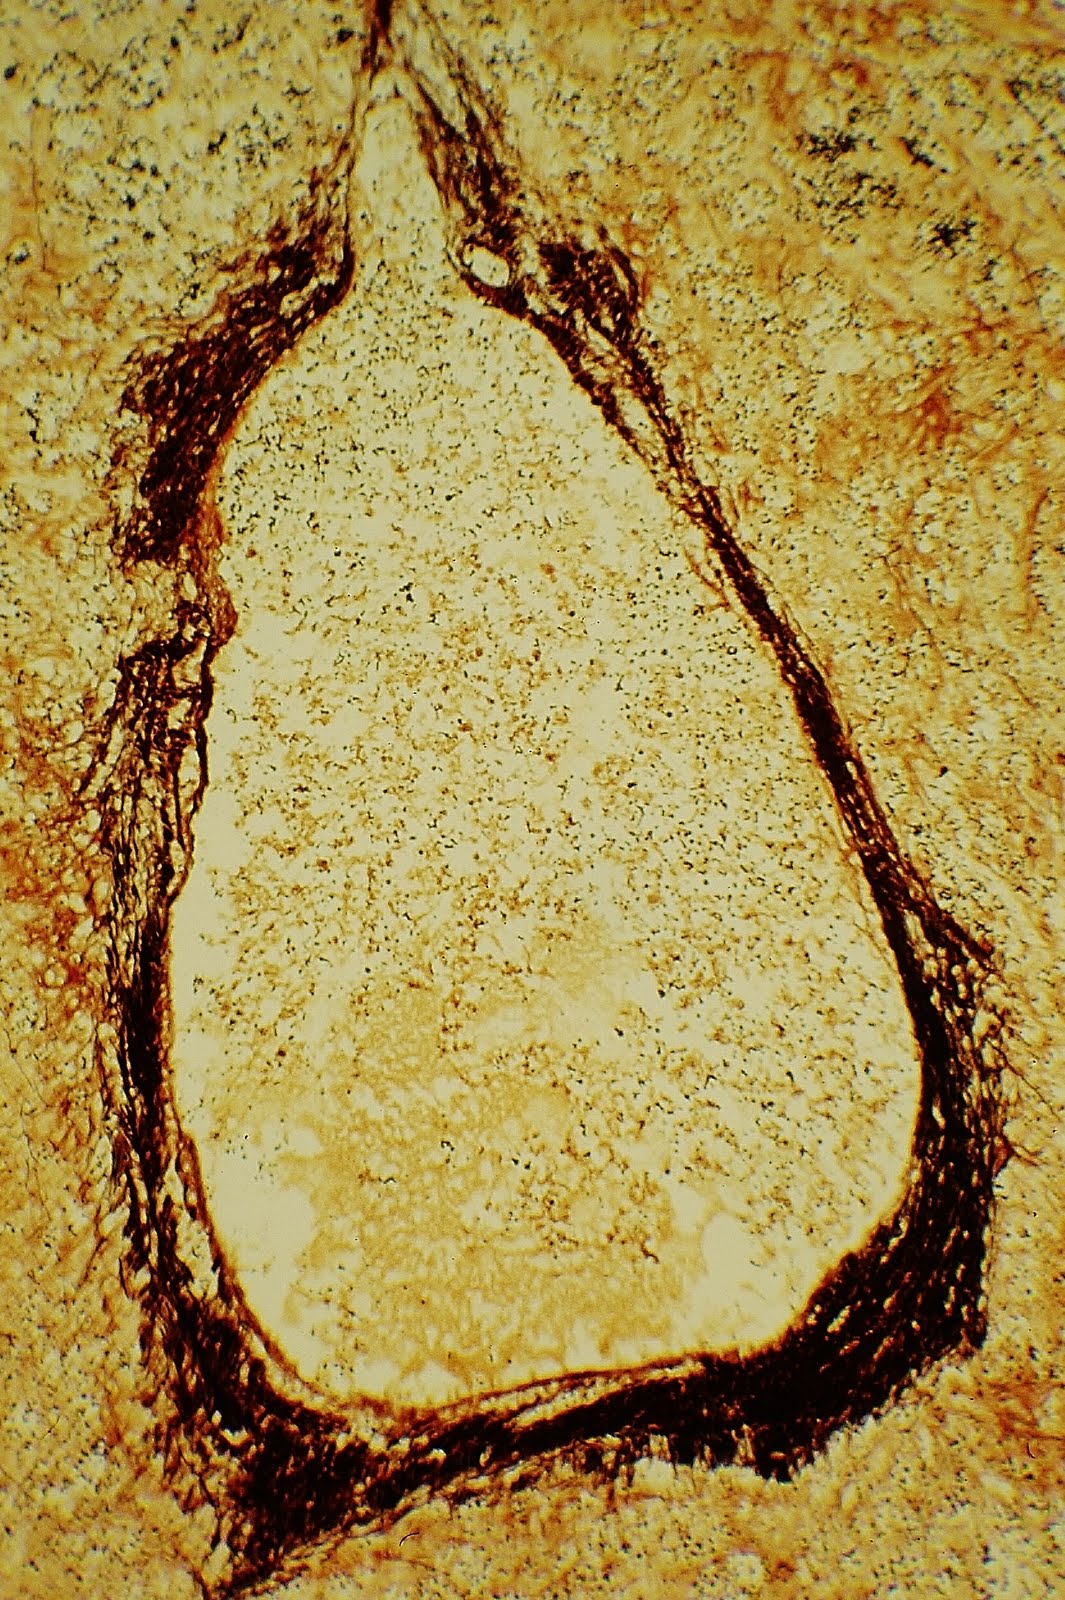

Criptococosis miocárdica.Técnica de PAS. SIDA.

Morfológicamente, las esporas de criptococo neoformans son redondas u ovoidales y miden entre 4 y 20 micras de diámetro, en función del tamaño de la cápsula celular. La respuesta inflamatoria es tanto menor cuanto más gruesa es la cápsula. La pared celular se tiñe con PAS-diastasa, plata metenamina (Gomori-Groccot) y con la técnica de Fontana-Masson. La cápsula no se tiñe con PAS ni con hematoxilina-eosina, pero como contiene mucopolisacáridos ácidos se puede teñir de azul con el Azul Alcián, de rojo con el Mucicarmín y metacromáticamente, de rojo, con el Azul de Metileno. El diagnóstico diferencial se tiene que realizar con otras micosis como la Blastomicosis o la Histoplasmosis. Existe una técnica inmunohistoquímica que utiliza suero anticriptococócico conjugado con inmunoperoxidasa.

Nótese, en la fotografía, la ausencia de respuesta inflamatoria por lo que el término "miocarditis criptococócica" parecería poco adecuado en esta situación; el concepto "criptococosis miocárdica" parece más adecuado en ausencia de una respuesta inflamatoria ortodoxa.

Prof.Garfia.A